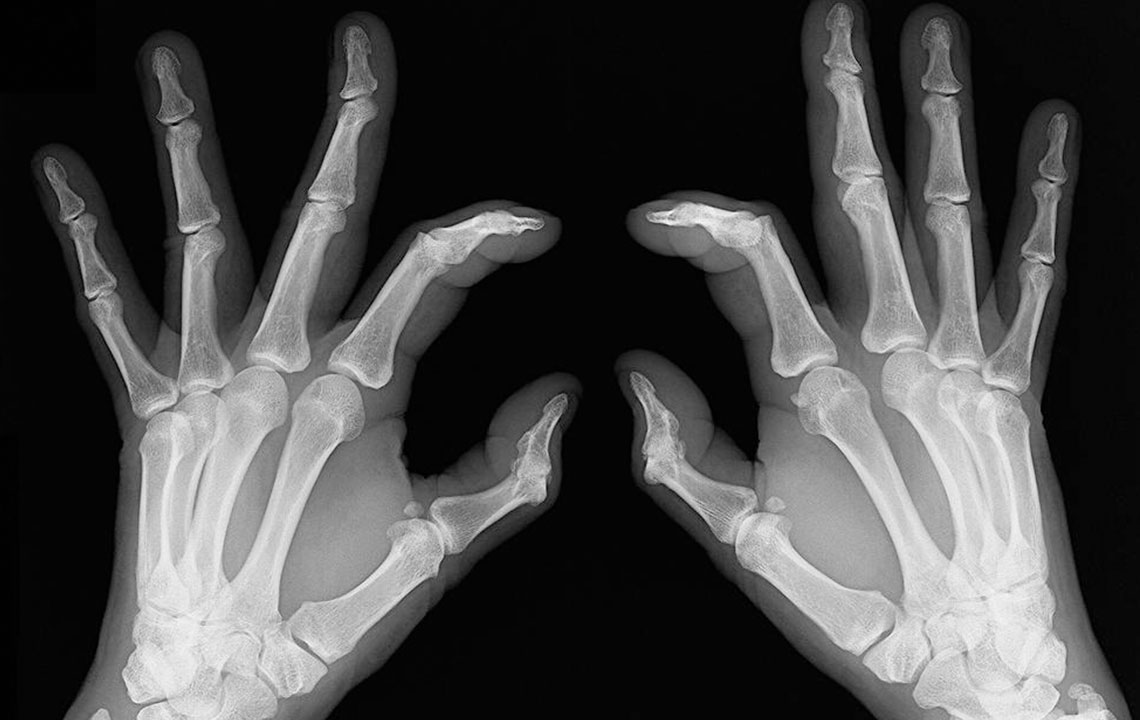

Rheumatoid arthritis causes chronic inflammation of joints, which results in joint pains, inflammation and bone deformation. It usually starts slowly with pain in some parts of the body that can come and go in the beginning and then spread within weeks or months. It is better in this day and age to always be aware of your health problems and not to ignore slightest of joint pains. The symptoms can vary from one person to another. Here are the many rheumatoid arthritis symptoms that you can check out.

• Bone deformation: Arthritis also attacks the bones and makes them crooked and stiff. Look out for signs of any subtle changes in your joints and test them for pain levels.